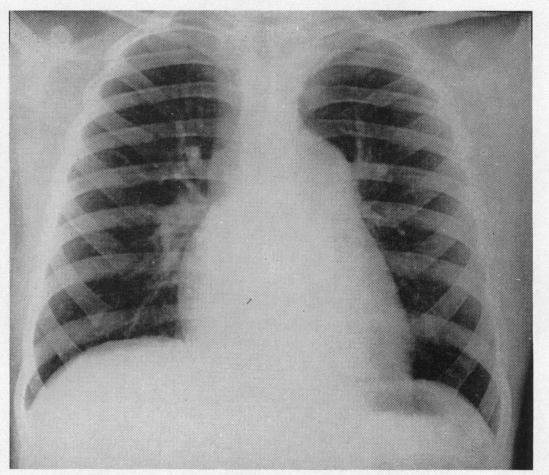

Pulmonary vascular patterns in pulmonary hypertension.

Br Heart J. 1957 Jul;19(3):353-65. doi: 10.1136/hrt.19.3.353.